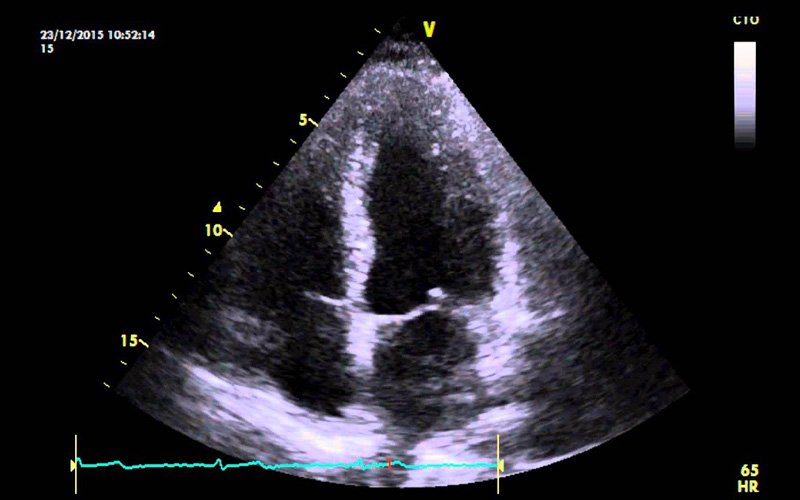

ECHO

An echocardiogram helps in getting a close look at the heart valves and how well they're working. This test allows doctors to have a closer look at the heart valves and cardiac function.